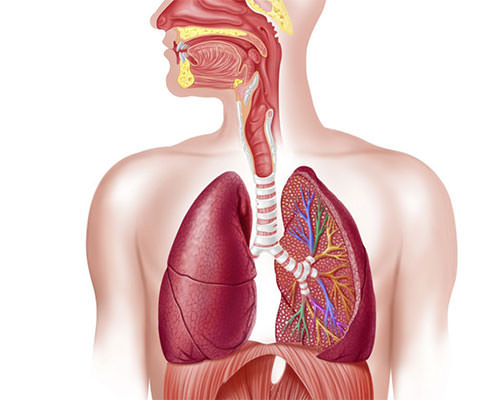

قیمت: 78٬000 تومان - دسته بندی فایل: پاورپوینتپاورپوینت دستگاه تنفسی انسان

فروش ویژه پاورپوینت حرفه ای دستگاه تنفسی انسان با تخفیف استثنایی فقط 92300 هزار تومان تعداد اسلاید : 41 اسلاید